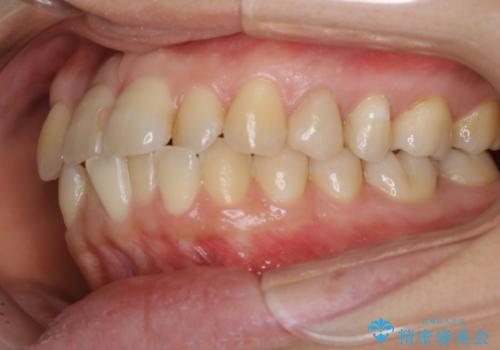

- 右上の2番目の歯が内側に入っているのと、下の前歯のがたつきが気になるとご相談にいらした方です。

上下左右の歯を後ろに動かして歯を並べるスペースを確保し、内側に入っていた歯を綺麗に並べ、前歯の中心もお顔の中心に合うようにしました。

矯正用アンカースクリューを埋入し、上下左右の歯を後ろに動かすことで歯を並べるスペースを作りました。

元々内側に倒れていた右下の奥歯は、ゴムかけを追加で行っていただくことによりしっかり起こすことが出来ました。